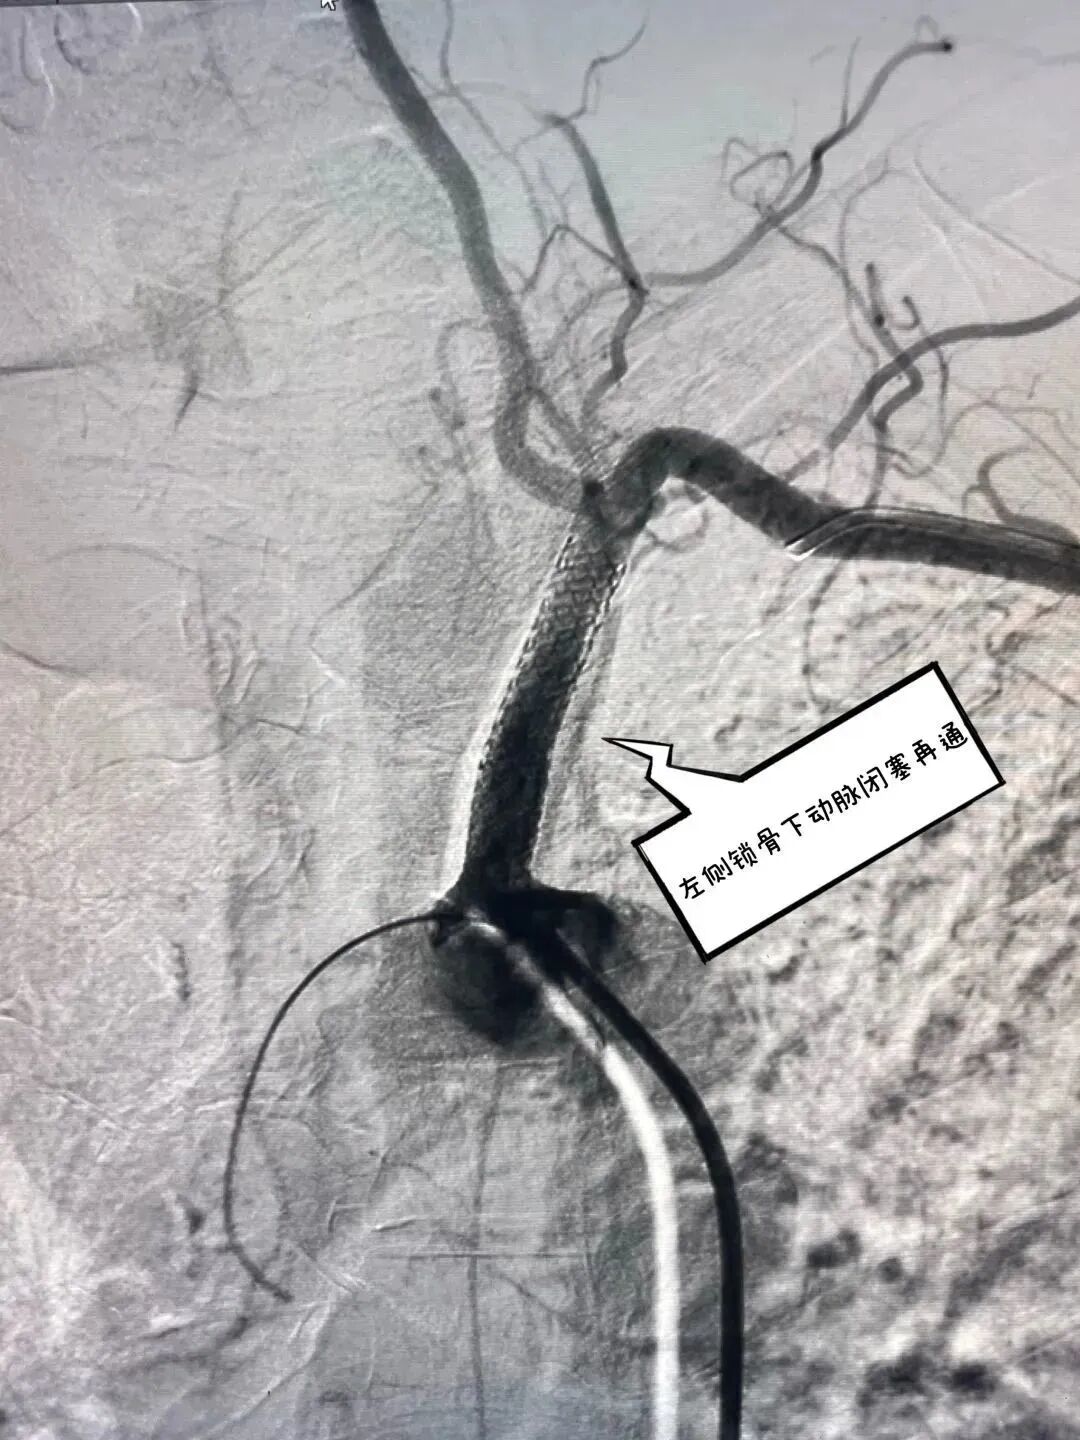

患者70岁老年男性,主因视物不清、反应迟钝入住神经内科,诊断脑梗死,经检查提示左侧锁骨下动脉闭塞,患者平素感头晕,左上肢发凉,双上肢血压相差30mmHg以上,为手术适应症,神经内科介入团队给予积极行介入血管再通治疗,因血管闭塞时间较长,导丝通过闭塞段困难,神经内科介入团队经股动脉,心内科吴刚主任帮助建立桡动脉通道,经股动脉、桡动脉双向成功开通闭塞血管,术后患者自述“头脑清醒,视物较前明亮,看世界亮了”。这是我院神经内科联合心内科完成首例双向开通锁骨下动脉血管,使我院介入水平上升新的高度!

主动脉弓造影提示左侧锁骨下动脉未见显影      经桡动脉逆向造影寻找血管真腔